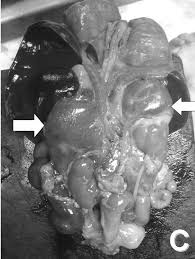

- Las niñas con una forma más grave a menudo tienen genitales anormales al nacer y es posible que reciban el diagnóstico antes de que aparezcan los síntomas.

El objetivo del tratamiento es devolver los niveles hormonales a lo normal o cerca de lo normal. Esto se hace tomando una forma de cortisol, casi siempre hidrocortisona. Las personas pueden necesitar dosis adicionales de medicamentos durante momentos de estrés, como por ejemplo una enfermedad grave o una cirugía. El médico determinará el sexo de un bebé con genitales anormales mediante un análisis cromosómico (cariotipo). Se puede practicar cirugía a las niñas con genitales de apariencia masculina durante la lactancia. Los esteroides empleados para tratar la hiperplasia suprarrenal por lo general no causan efectos secundarios, como obesidad o huesos débiles, ya que las dosis reponen las hormonas que el cuerpo del niño no puede producir. Es importante que los padres informen sobre los signos de infección y estrés al pediatra, dado que el niño puede necesitar más medicamento. Los esteroides no se pueden suspender de manera súbita, ya que hacer esto puede provocar una insuficiencia suprarrenal.